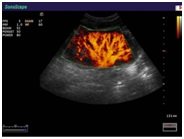

Компания SonoScape  уделила особое внимание допплеровским режимам и является экспертом в своем классе, что позволяет с легкостью, но в то же время с уникальной точностью проводить исследования с постановкой наиболее точного диагноза.

Ультразвуковые исследования, доплеровское сканирование сосудов в Медицинском центре «АКВА МЕД МАРИН» выполняется при помощи первого и единственного аппарата в Керчи SonoScape S40Exp (экспертного класса, который оснащен множеством новейших функций, многократно улучшающих качество и информативность УЗИ-исследования).

• доплерография сосудов внутренних органов;

• исследования артериальных и венозных сосудов практически в любой области тела, при помощи 7 различных режимов допплерографии сосудов;

• расширенное цветовое допплеровское картирование;